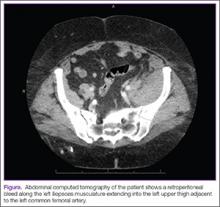

Clinical examination showed a well-healed scar and pristine stump under her right hemipelvis. Passive range of movement of her left hip was painful for all movements, reduced at flexion (90º) and internal (10º) and external rotation (5º). Examination of her left knee was normal, with a full range of movement and no joint-line tenderness. A high body mass index (>30) was noted. Radiographic imaging confirmed significant OA of the hip joint (Figure 1). Informed consent was obtained for THA. The implants were selected—an uncemented collared Corail Stem (DePuy, Warsaw, Indiana) with a stainless steel dual mobility (DM) Novae SunFit acetabular cup (Serf, Decines, France), with bearing components of ceramic on polyethylene. A preoperative computed tomography (CT) scan of the left hip was performed (Figure 2) to aid templating, which was accomplished using plain films and CT images, with reference to the proximal femur for deciding level of neck cut, planning stem size, and optimizing length and offset, while determining cup size, depth, inclination, and height for the acetabular component.

CT scanning is routinely performed in our institution to optimize preoperative templating. The preoperative CT images enable accurate planning, notably for the extramedullary reconstruction,13 and are used in addition to acetates and standard radiographs. This encourages preservation of acetabular bone stock by selecting the smallest suitable cup, reduces the risk of femoral fracture by giving an accurate prediction of the stem size, and ensures accuracy of restoring the patient’s offset and length. Although limb-length discrepancy was not an issue for this patient with a single sound limb, the sequalae of excessively increasing offset or length (eg, gluteus medius tendinopathy and trochanteric bursitis) would arguably be more debilitating than for someone who could offload weight to the “good hip.” For these reasons, marrying the preoperative templating with on-table testing with trial prostheses and restoring the native capsular tension is vital.